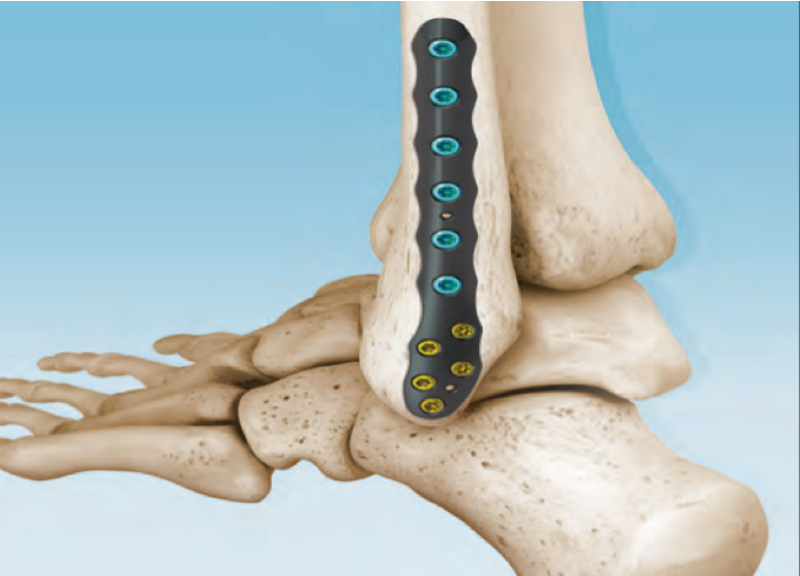

CONMED Foot and Ankle offers tailored innovation and simplified solutions. Explore our complete portfolio of arthroplasty, biologic, fixation, implant, suture anchor, and instrumentation offerings for foot and ankle surgery.

Dr. Early - First MTP Fusion Technique with Metatarsal Head Bone Loss